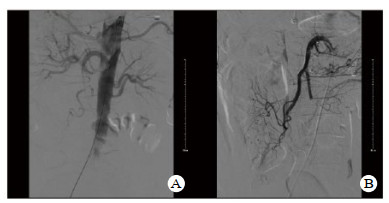

2 结果本组24例早期介入治疗患者,共19例患者肠梗阻症状逐渐缓解,临床治愈,治愈率79.2%。术后白细胞计数、D-二聚体指标与术前比较差异有统计学意义(P < 0.05),见表 1。其中18例MAET患者有经肠系膜上动脉造影后显示主干栓塞12例,空回肠动脉栓塞6例,经腔内介入治疗梗阻血管15例成功再通或侧枝开放(图 1),6例造影显示MVT患者经腔内介入治疗4例血栓基本溶解。另有3例MAET、2例MVT患者肠梗阻症状持续加重予以48 h内行剖腹探查术,予以肠系膜上动脉切开取栓3例,肠系膜静脉切开取栓1例,小肠部分切除4例,全小肠切除1例,其中3例术后恢复良好,2例因感染性休克、循环衰竭,围手术期死亡。

| 图 1 患者术前术后肠系膜上动脉造影结果(A:介入治疗术前造影提示肠系膜上动脉闭塞;B:介入治疗术后造影提示肠系膜上动脉开通) |